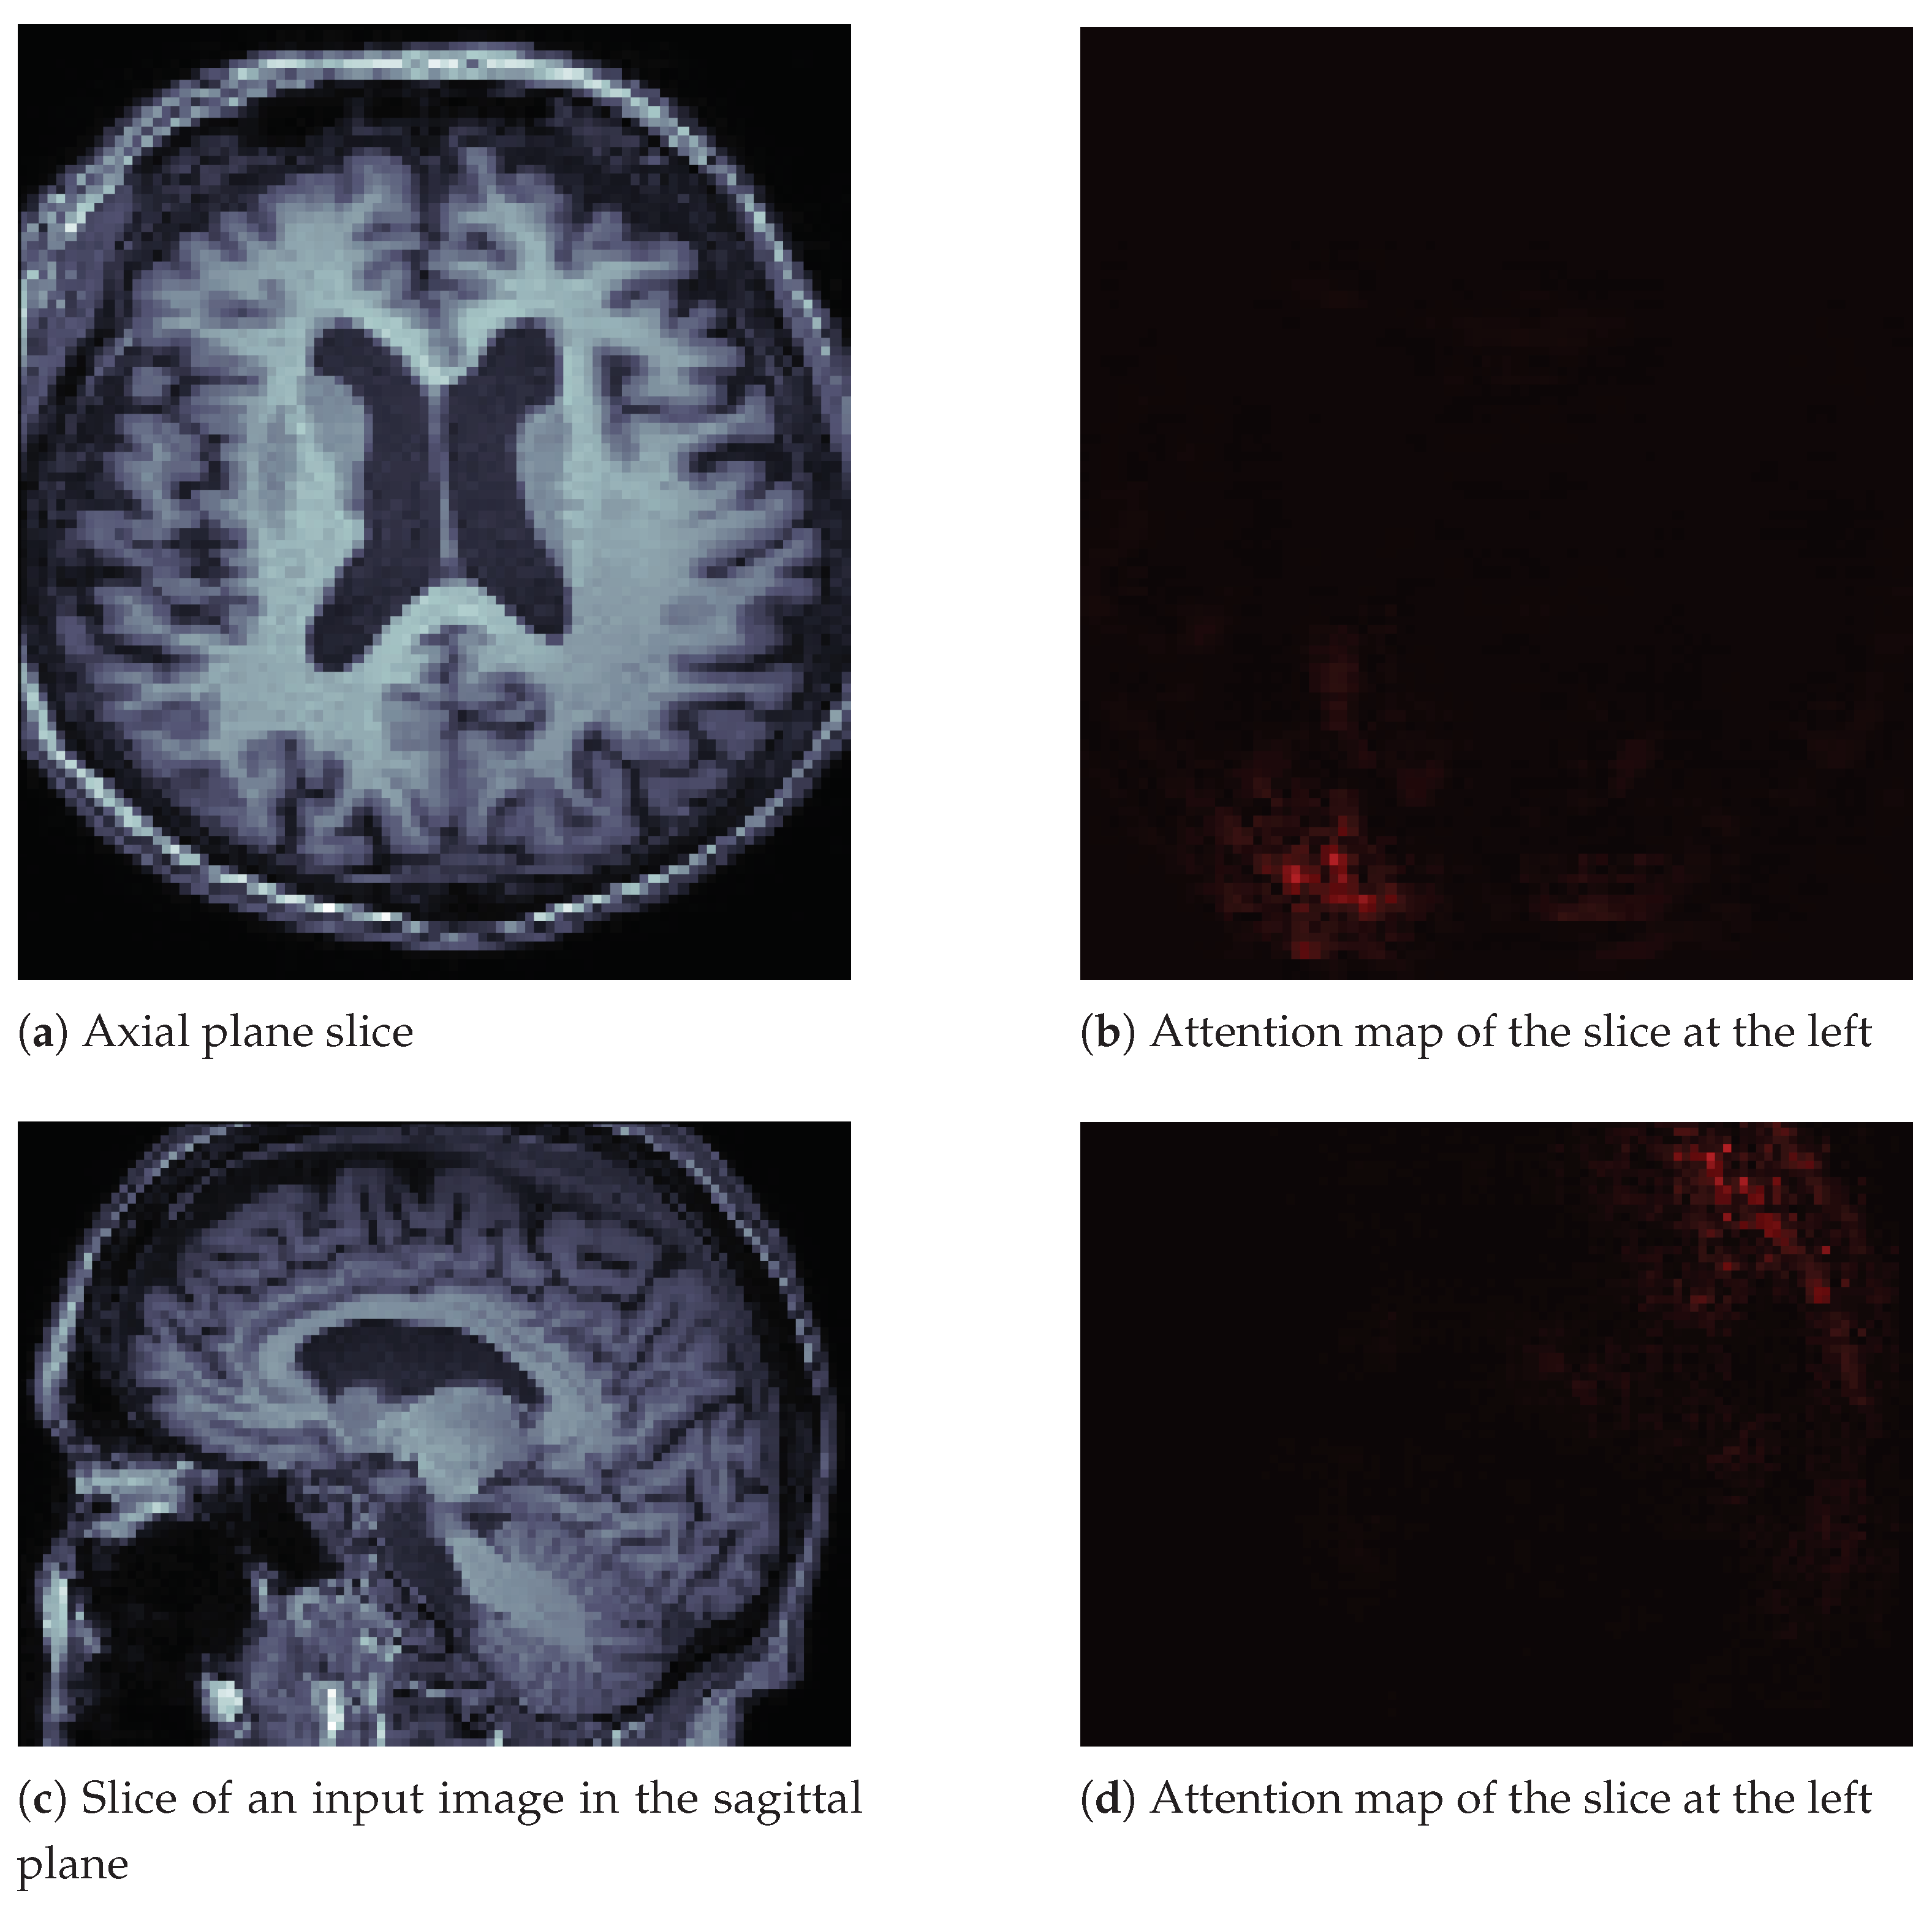

Additionally, we include the attention map for a non-affected individual in Figure 7 on page 14. The difference from the image in Figure 6 is that this image seems to generate less attention from the neural network. We observed the same behavior in other images of healthy people.

Figure 7.

Image slices and their attention maps from an MRI of a healthy person.

The M3d-CAM tool allowed us to better study the resulting neural network and generate new hypotheses to improve our current work. Furthermore, by incorporating the attention maps, we added a layer to our work that widens what we can achieve with our current and future classification systems. As an example, we now consider the use of brain segmentation. It is essential to include more visualization tools for neural networks that would allow debugging and understanding these architectures in depth.